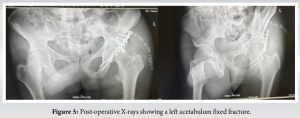

He was then booked, prepared, and planned for the theater 7 days later. He then underwent left acetabulum open reduction and internal fixation for the displaced posterior wall fracture under general anesthesia. We placed him in the right lateral . We then cleaned and draped the operative site under sterile conditions. The left acetabulum was approached using the Kocher–Langenbeck approach. The gluteus minimus was noted to be torn but attached to the large posterior wall fragment. The fracture was then reduced, and a spring plate and “tiara” plate were then applied to the fracture site, and screws were inserted to maintain the reduction. The reduction was acceptable under fluoroscopy imaging. Copious irrigation was carried out, and the wound was closed in layers, and a dry dressing was applied to the area. Control X-rays (Fig. 5) were ordered, and his post-operative hemoglobin level was normal. Postoperatively, he began non-weight-bearing physiotherapy and was discharged in a wheelchair and on anticoagulation. At the 2-week follow-up, his surgical wounds healed without complications, and the 6-week follow-up X-rays showed healing fractures. Post-operative rehabilitation included 6 weeks of wheelchair use followed by ambulation with crutches.